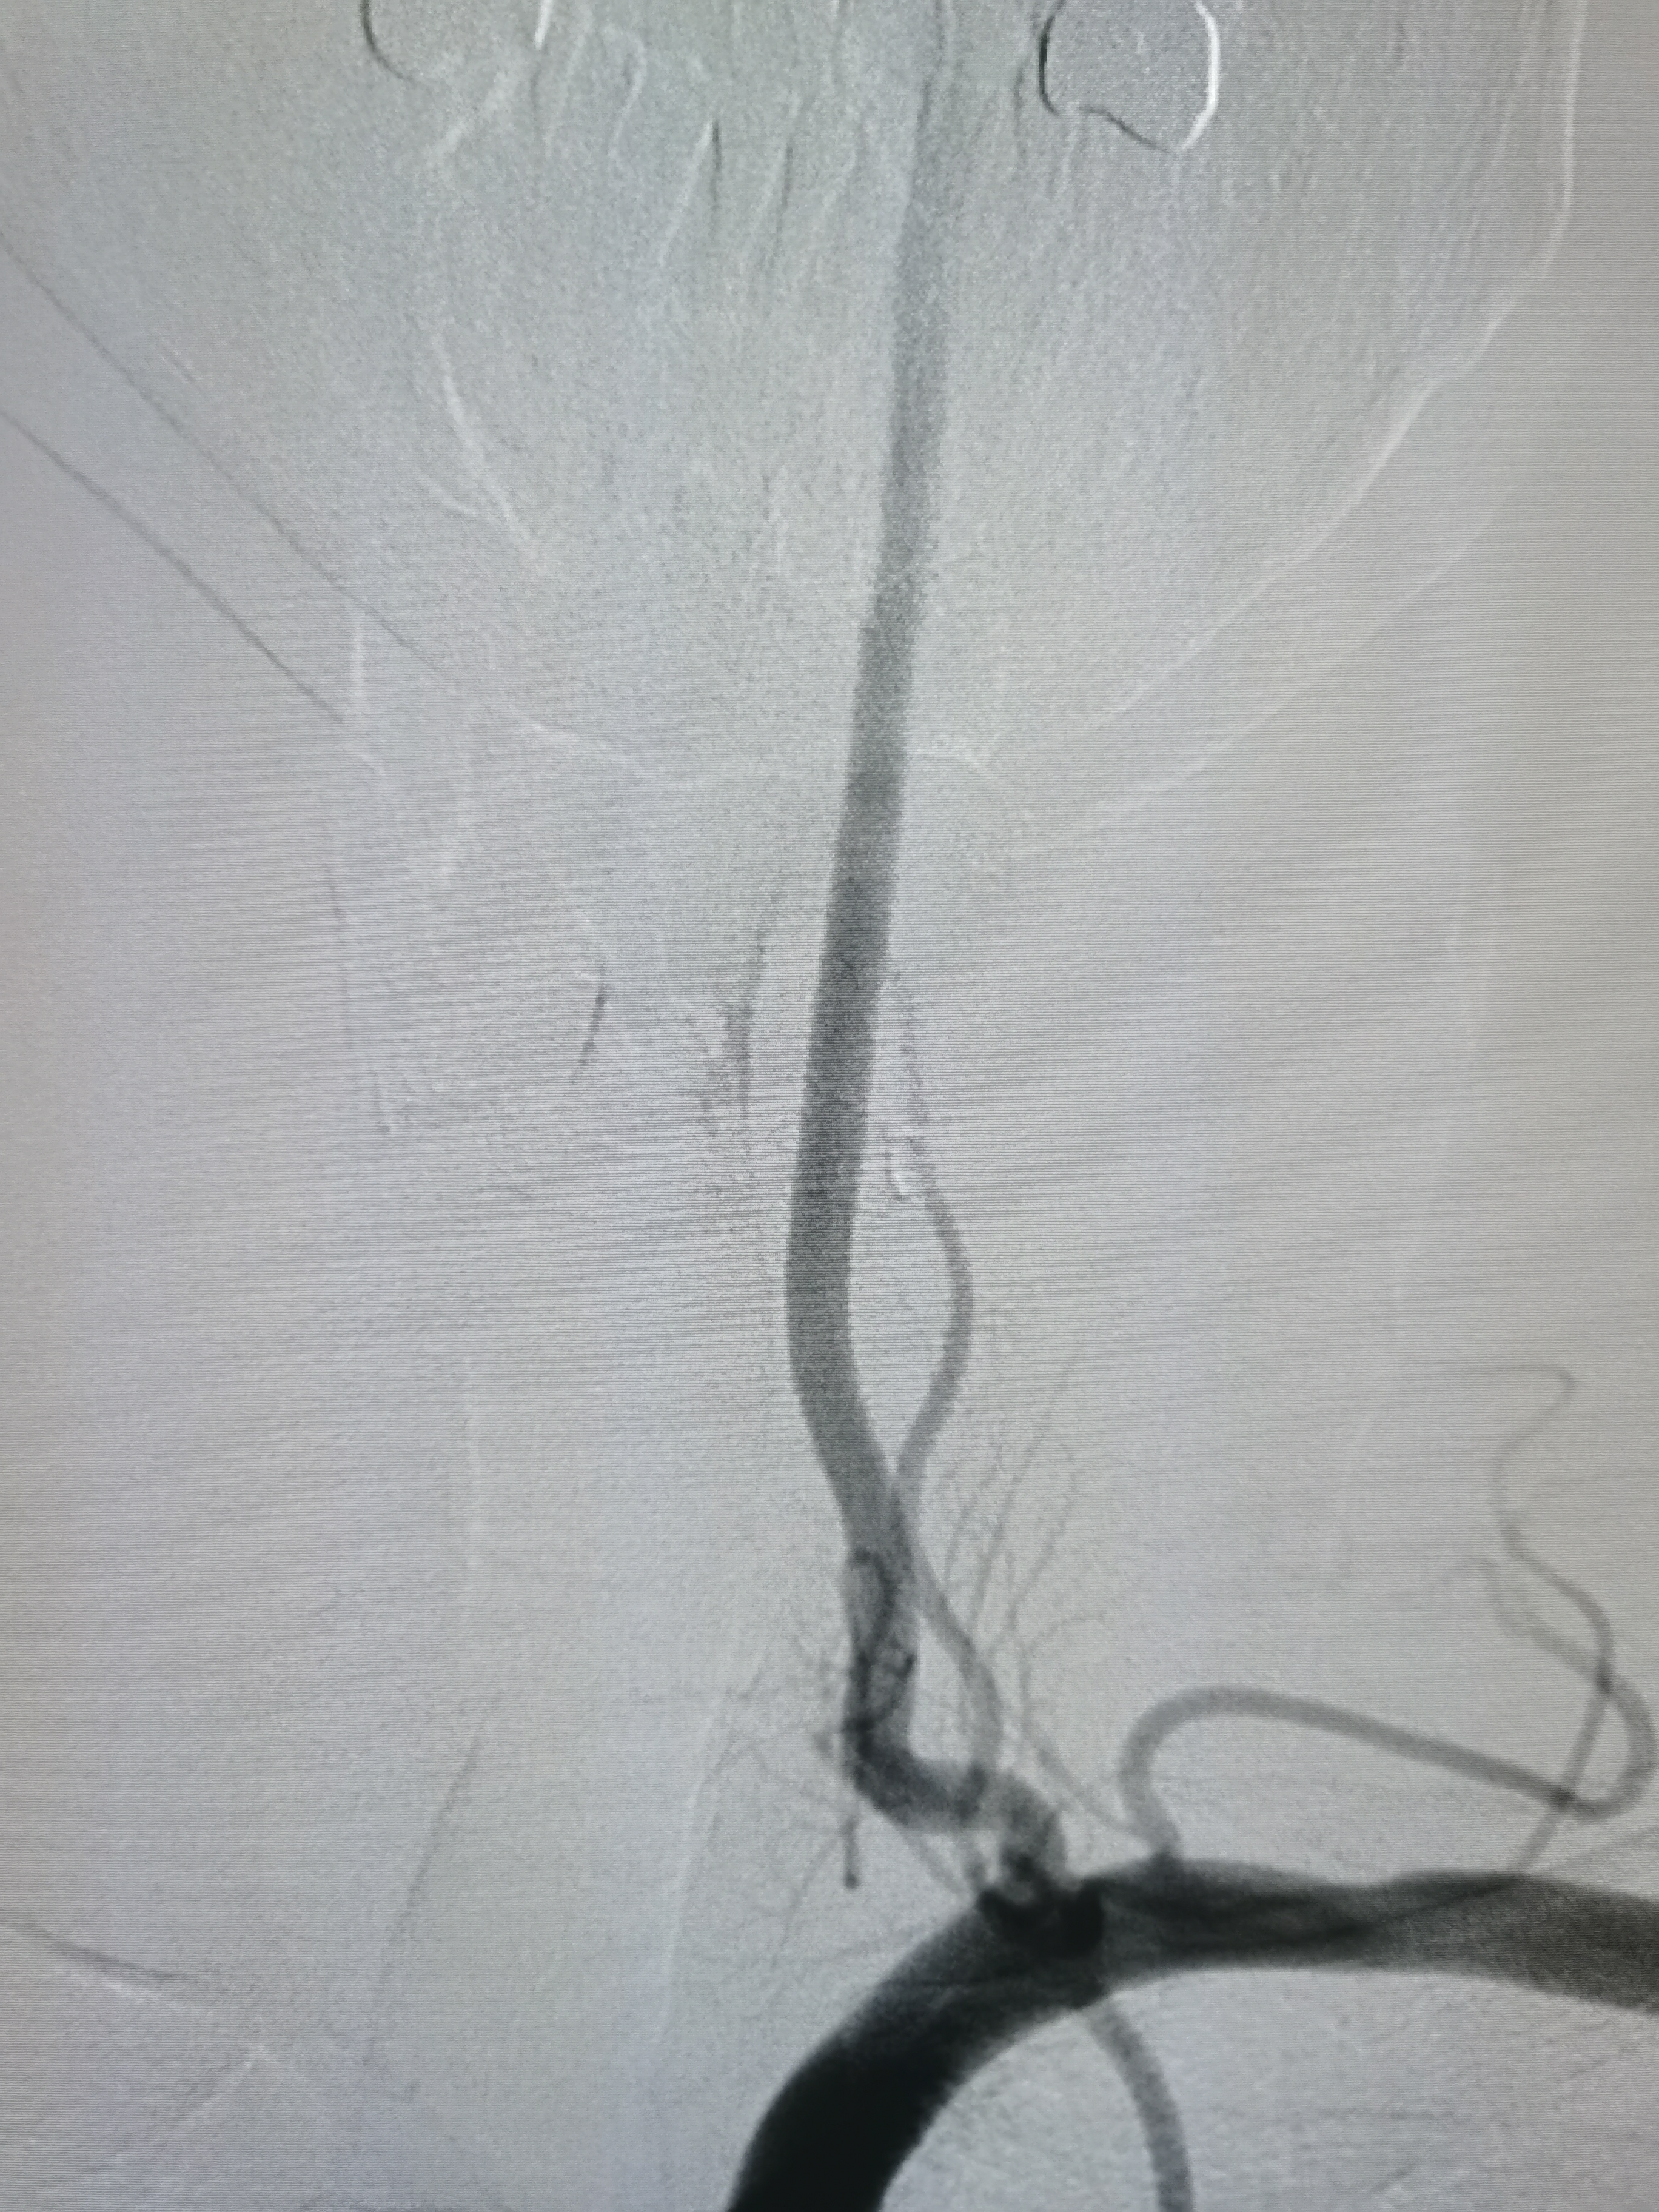

全麻后,将8F导引导管及中间导管顺利到位,建立路径,在路径图下微导丝携微导管顺利通过病变。

微导管确认位于真腔,交换入Transend300导丝。

2.0/15球囊扩张闭塞处。

扩张后造影见近端显影,远端血管仍闭塞。

将球囊前送,再次加压扩张。